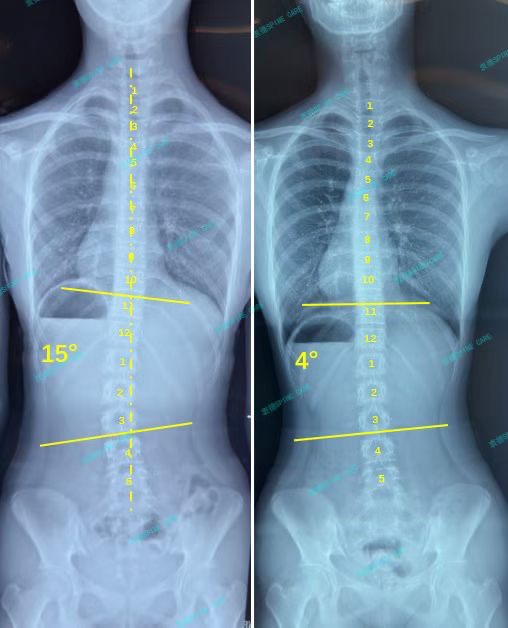

衷德脊柱,我们只关注侧弯保守治疗~

Zhongde Spine, bending no breaking ~